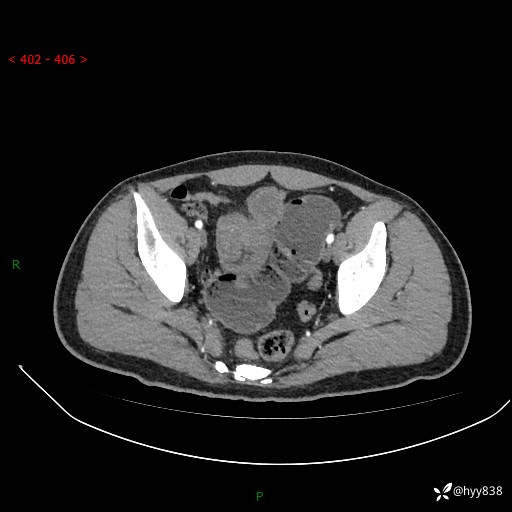

年轻男性,腹痛5月余。除了肠梗阻,你还能看到什么---结果公布~

现病史:患者于5月前无明显诱因开始出现腹痛,上明显,为间断性胀痛不适,无畏寒发热,无心慌气促等特殊不适,遂来我院。我院门诊遂以“腹痛原因待查”收入我科。 起病以来,患者精神、饮食、睡眠欠佳,大小便正常。体力体重无明显变化。

腹部CT增强扫描(动脉期+静脉期)